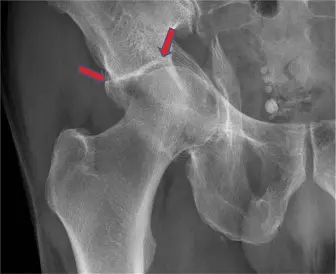

الشكل 1: صورة بالأشعة السينية المائلة (جوديت) للحق الأيسر تظهر نمط كسر معقد ومتفتت. -